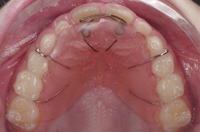

• Quá trình điều trị chỉnh nha không chỉ là nắn chỉnh các răng về vị trí mong muốn, mà nó còn gồm cả một giai đoạn cuối được gọi là "giai đoạn duy trì". Sau khi các răng đã di chuyển đến đúng vị trí, bệnh nhân sẽ phải tiếp tục mang một loại khí cụ để duy trì kết quả đạt được, nhằm giữ các răng ở đúng vị trí ổn định.

• Điều trị duy trì là rất quan trọng để ổn định sự vững chắc của xương và răng, vì sau khi tháo khí cụ chỉnh hình, mô nha chu cần có thời gian để tổ chức lại cấu trúc, nướu và xương xung quanh tiếp tục điều chỉnh. Mặt khác, áp lực mô mềm luôn có khuynh hướng đẩy các răng trở về vị trí cũ.

• Khí cụ duy trì có thể là khí cụ cố định hay tháo lắp, hoặc có thể chỉ là một đoạn dây kim loại được dán vào mặt trong của các răng. Mang những khí cụ này theo đúng hướng dẫn là cách bảo đảm tốt nhất để ngăn ngừa sự tái phát trong CHRHM. Thời gian mang khí cụ duy trì thay đổi tùy từng trường hợp, có thể kéo dài 6 tháng hoặc lâu hơn để ngăn ngừa sự dịch chuyển trở lại của răng.